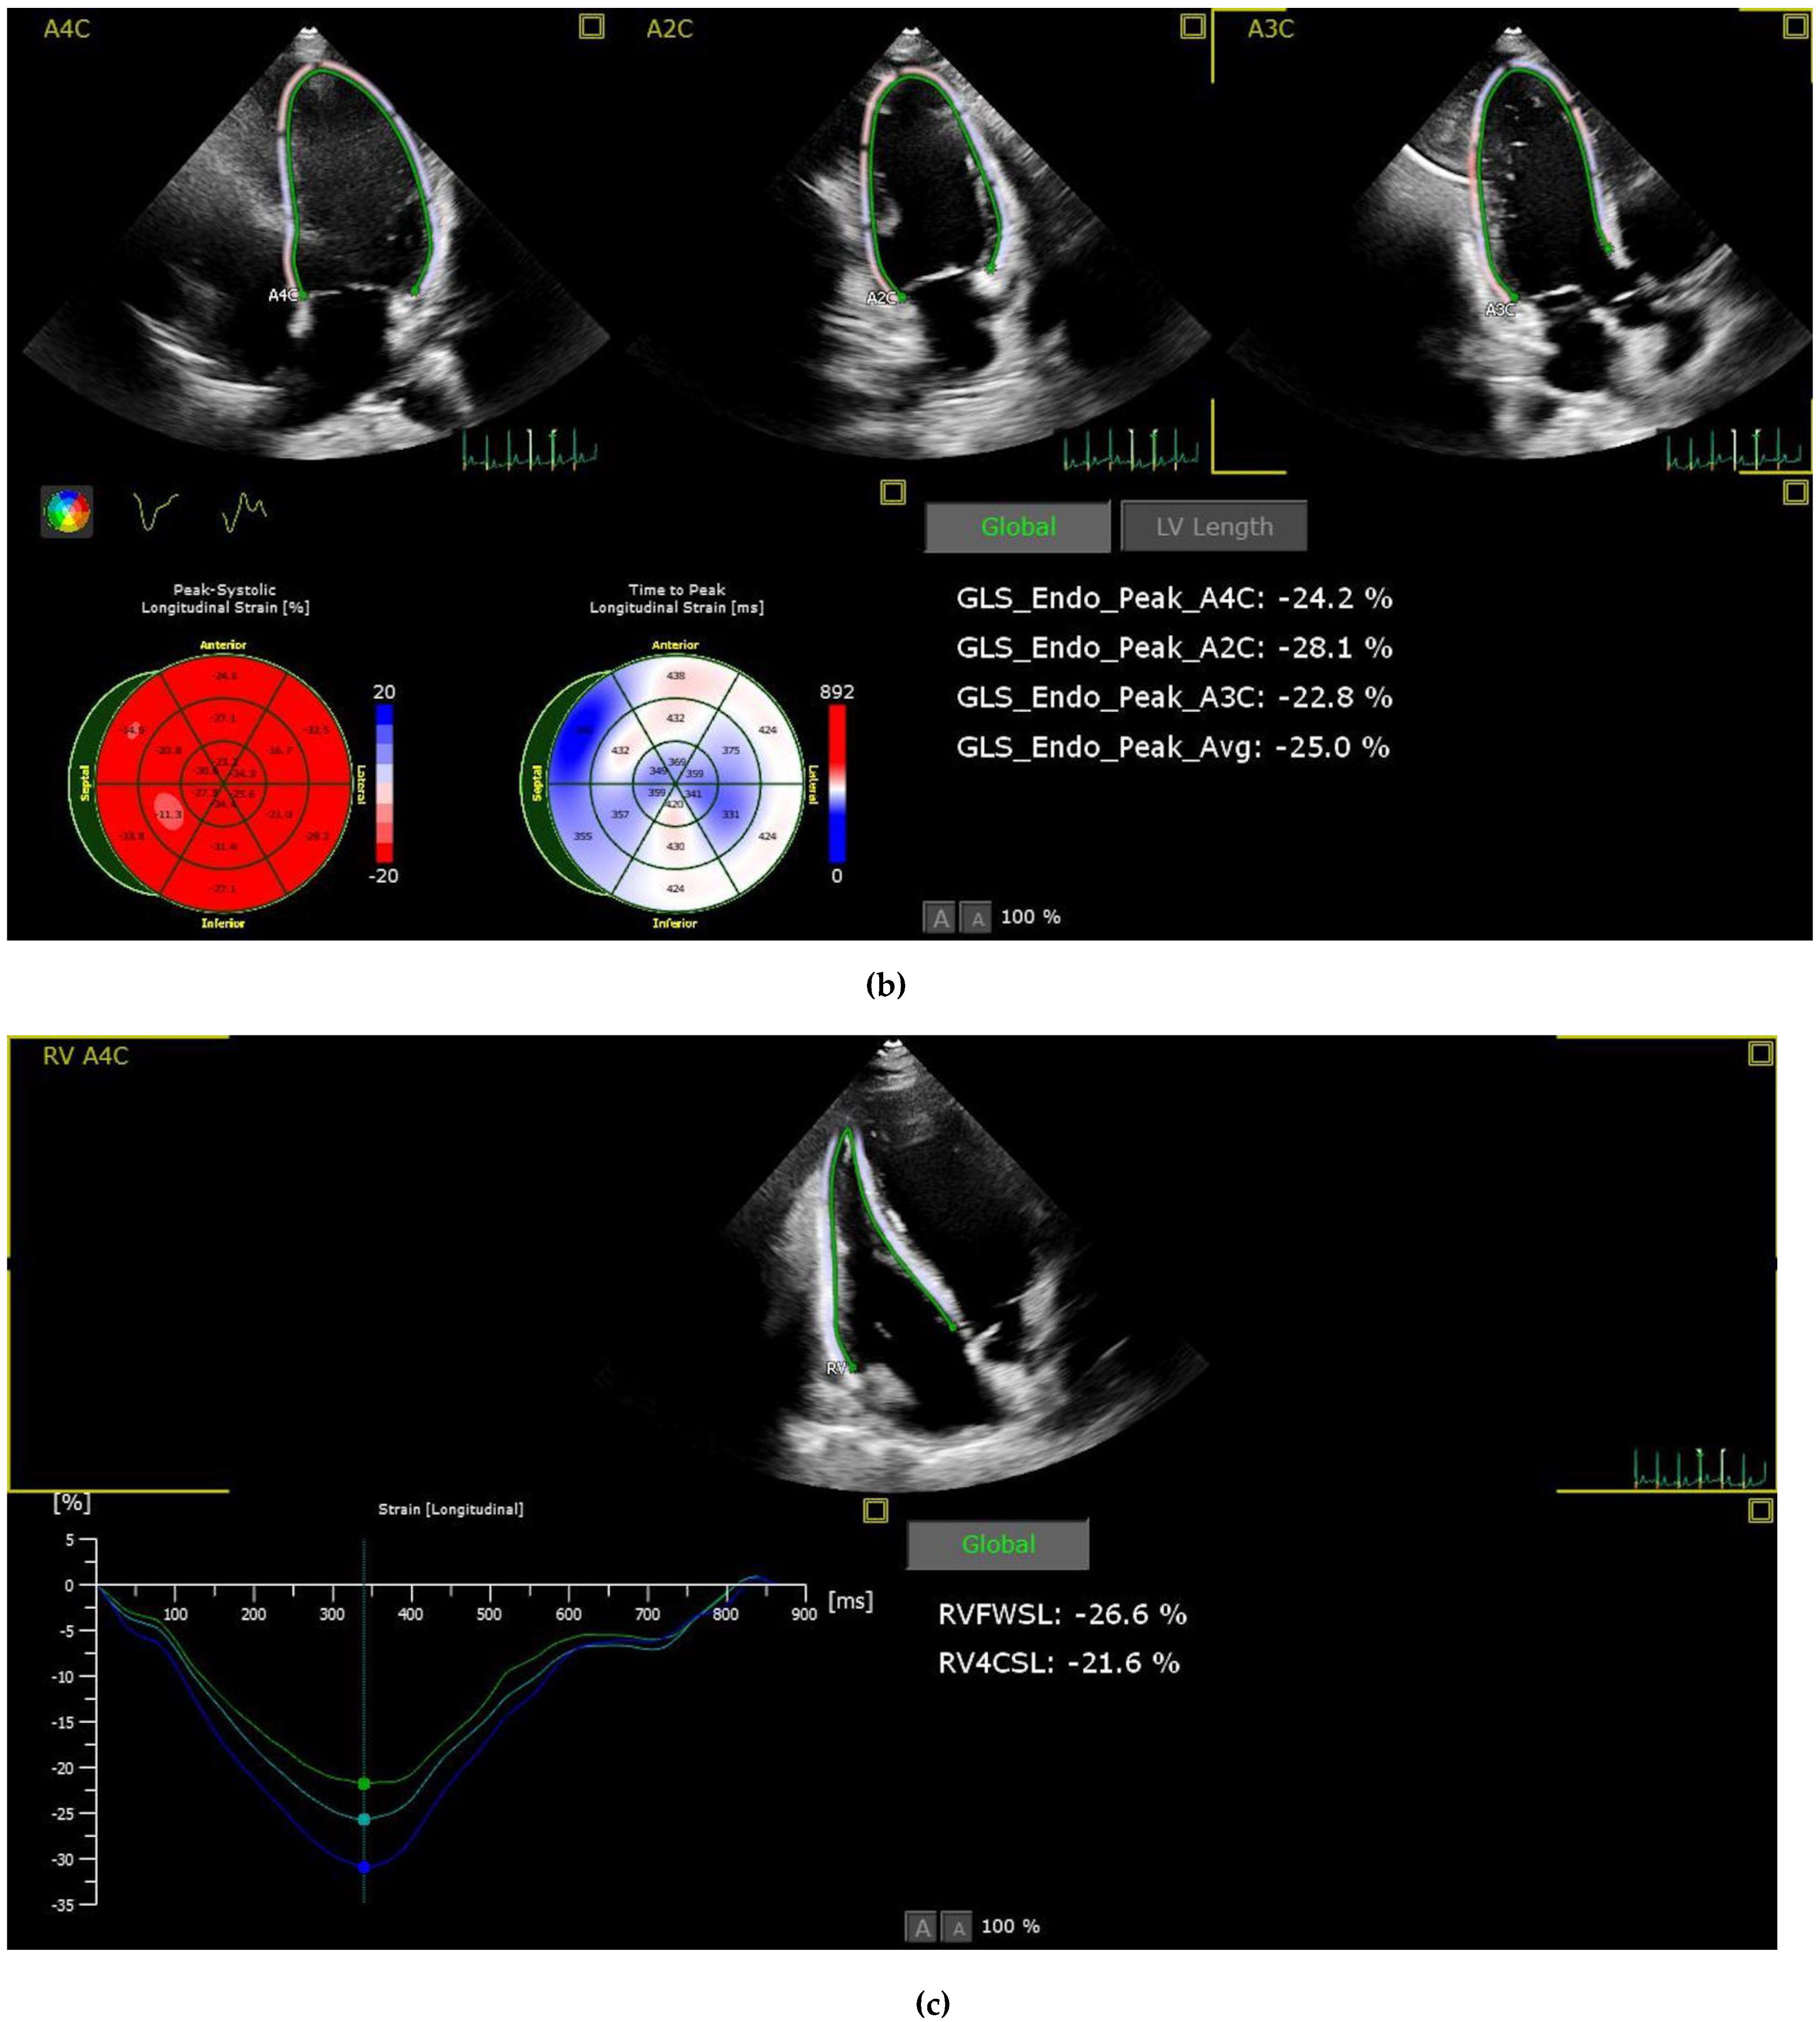

2.3. Strain Analysis

| LV-GLS | −20.8 ± 4.1 | −20.9 ± 2.6 | 0.803 |

| RV-FWSL | −29.5 ± 5.5 | −27.9 ± 5.9 | 0.096 |

| RV-GLS | −25.5 ± 6.9 | −24.4 ± 5.2 | 0.297 |

| LVEF (%) | 65 ± 4.1 | 65.4 ± 4.2 | 0.594 |